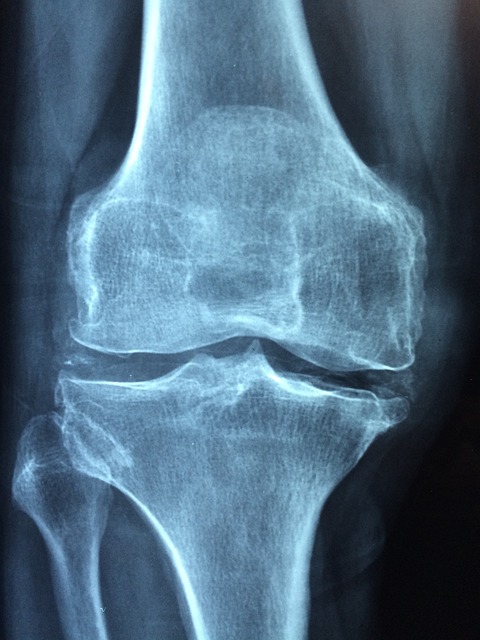

오늘은 저희 모두의 건강에 중요한 역할을 하는 콘드로이친(condroitin)에 대해 자세히 알아보려고 합니다. 콘드로이친은 관절 건강에 긍정적인 영향을 미치는 자연물질로서, 많은 사람들이 그 효능을 인지하고 있습니다. 특히, 이 물질은 관절과 연골의 건강을 유지하는 데 필수적인 역할을 하며, 손상된 연골을 복구하고 통증을 완화하는 등 다양한 기능을 수행합니다.

우리 몸에서 콘드로이친은 연골 조직 내에서 발견되는 주요 성분 중 하나로, 연골은 우리의 관절에서 움직임을 매끄럽게 도와주는 중요한 역할을 합니다. 그리고 이 콘드로이친은 이 연골 조직의 건강을 유지하고, 증진시키는 데 중추적인 역할을 합니다. 이런 점에서 우리는 콘드로이친의 중요성을 절대 무시할 수 없습니다.

콘드로이친은 연골 조직을 형성하고 유지하는 데에 필수적인 역할을 합니다. 연골은 관절을 보호하며 완충하고 충격을 흡수하는 역할을 하므로, 콘드로이친은 이를 통해 관절 건강을 유지하는 데 큰 도움을 줍니다. 이는 특히 노화와 관련된 연골의 변화를 관리하는 데 중요합니다.

연령이 들면서 우리의 연골은 자연적으로 손상되거나 약해질 수 있습니다. 이때 콘드로이친은 연골 조직의 재생을 촉진하고, 손상된 연골을 복구하여 관절의 기능을 개선하는 데 큰 도움을 줄 수 있습니다. 이는 노화와 함께 오는 자연적인 연골의 손상을 관리하고, 건강한 관절 기능을 유지하는 데 필수적입니다.

관절염 등의 관절 질환은 심한 통증을 유발할 수 있습니다. 콘드로이친은 이러한 관절 통증을 완화하고, 염증을 감소시키는 데 효과적인 역할을 합니다. 이로 인해 우리는 일상생활에서 더욱 편안하게 활동할 수 있습니다. 관절 기능 향상: 콘드로이친은 관절의 유연성과 움직임을 개선하는 데 큰 도움을 줄 수 있습니다. 이를 통해 일상생활에서 더 편안하고 활동적인 삶을 즐길 수 있게 됩니다. 이는 우리가 일상적인 활동을 수행하거나 운동을 할 때 움직임을 원활하게 하며, 통증을 줄이는 데 큰 도움을 줍니다.

콘드로이친은 연골 조직을 보호하는 역할을 합니다. 연골은 일상적인 활동이나 운동 중에도 충격을 흡수하고 관절을 보호하는 역할을 하므로, 콘드로이친의 섭취는 연골의 손상을 예방하고 유지하는 데 도움을 줄 수 있습니다. 이는 우리의 일상 생활과 운동 성능을 향상하는 데 크게 기여합니다.

관절 질환과 관련된 염증은 통증과 불편을 유발할 수 있습니다. 콘드로이친은 염증을 감소시키는 작용을 가지고 있어, 관절의 염증을 완화하고 통증을 줄여줄 수 있습니다. 이는 통증을 관리하고, 불편을 최소화하는 데 매우 중요한 역할을 합니다.